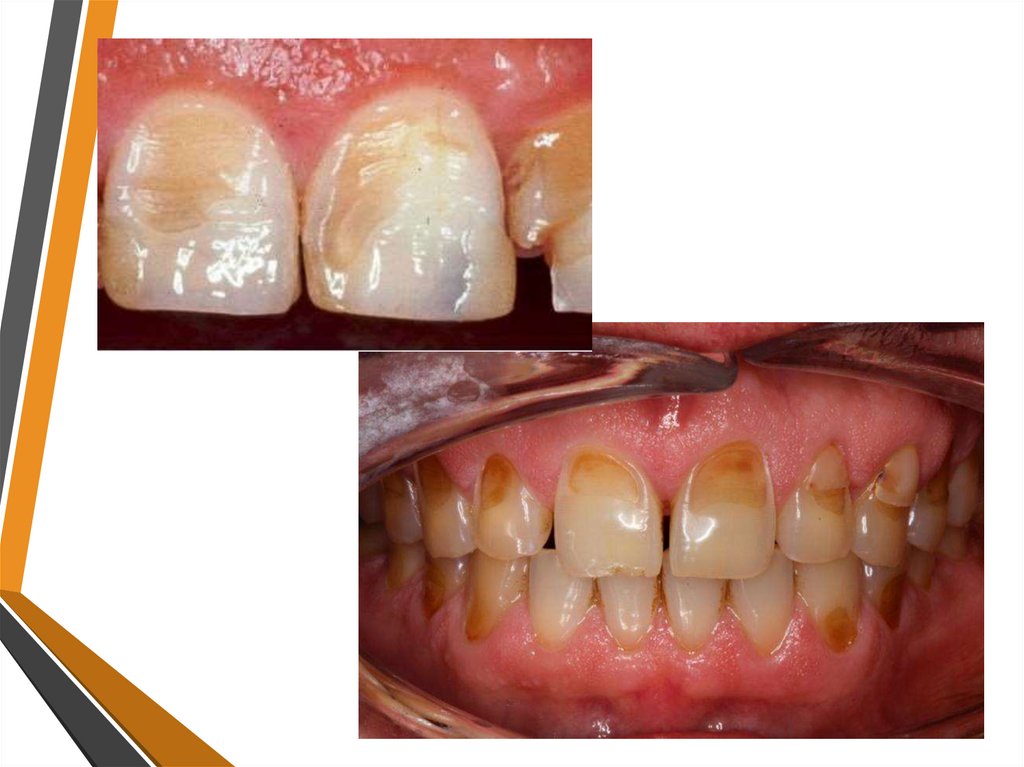

11. ЭРОЗИЯ ЗУБОВ

• Эрозия — это дефект твердых тканей зуба с локализацией

на вестибулярной поверхности, имеющий форму блюдца.

• Локализация. Эрозии твердых тканей зубов появляются

преимущественно на симметричных поверхностях

центральных и боковых резцов верхней челюсти, а также

на клыках и малых коренных зубах обеих челюстей.

Дефекты располагаются на вестибулярных поверхностях в

области экваторов зубов. Поражение симметричное.

Практически не встречаются эрозии на больших коренных

зубах и на резцах нижней челюсти.

• Клиническая картина. Эрозия представляет собой

овальный или округлый дефект эмали, расположенный на

наиболее выпуклой части вестибулярной поверхности

коронки зуба. Дно эрозии гладкое, блестящее и твердое.

Эрозия эмали в отличие от других видов истирания в

большинстве случаев характеризуется выраженными

болевыми ощущениями при действии различного рода

факторов, особенно холодного воздуха и химических

раздражителей. В активной стадии жалоб больше, чем в

стабилизированной.